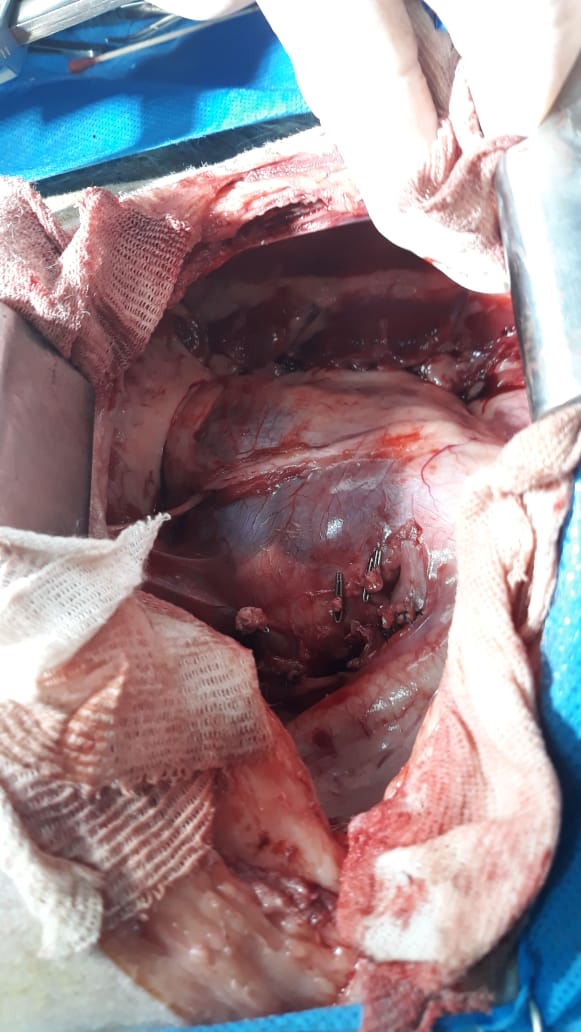

se justifica, por ejemplo linfonodos. Si el paso siguiente es la biopsia deberemos tener en cuenta

la diferencia entre incisional o escisional: la primera permite la extracción de una pequeña parte

del tumor y la misma no afecta el comportamiento o la evolución de la enfermedad debido a que

no se modifica el microambiente tumoral; por otro lado la biopsia escisional permite mayor

cantidad de tejido, grado y definición arquitectural más exacta, pero en ciertos tumores puede

modificar el comportamiento, un ejemplo es el mastocitoma sobre todo el de alto grado.

Biopsia escicional: la técnica consiste en realizar la tumorectomía sin margen quirúrgico

por lo cual no hay que confundir con la cirugía y es solo un procedimiento diagnóstico y rara vez

resolutivo en las patologías oncológicas. Hay que entender que al modificar el microambiente

tumoral cuando uno realiza una biopsia escicional no teniendo en cuenta los márgenes, el

procedimiento puede modificar a futuro la terapéutica o el comportamiento de la enfermedad

oncológica, por lo cual es necesario plantearse el costo beneficio de realizarla o no.